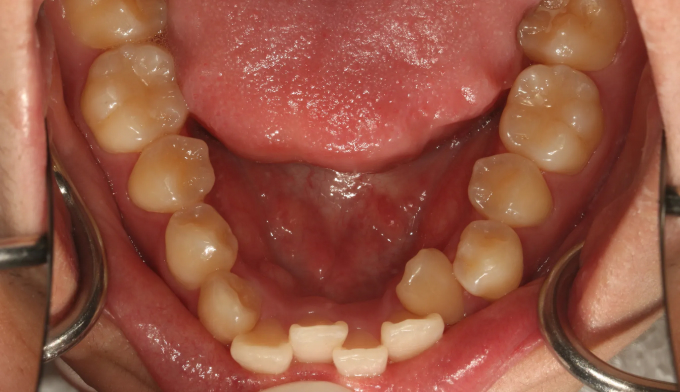

이가 배열될 공간이 부족해서 삐뚤빼뚤하게 나왔습니다.

돌출형인 얼굴을 고려하여도 어차피 발치교정이 필요할것 같아서 성인이 된 이후에 치료할것을 권유하였습니다.

하지만 본인 스스로가 고르지 못한 앞니에 컴플렉스를 가지고 있었고, 어차피 교정할거면 빨리 진행하길 원했습니다.

가지런한 앞니는 성장중인 학생들에게 큰 자신감을 줍니다.

총 치료기간은 19개월 입니다.